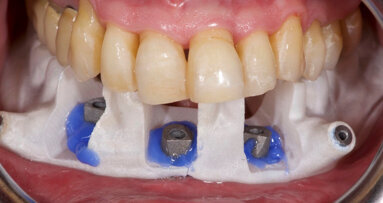

Nowadays, virtual planning and the assisted placement of implants in 3-D positions relative to the bone, soft tissue and final planned prosthesis are ...